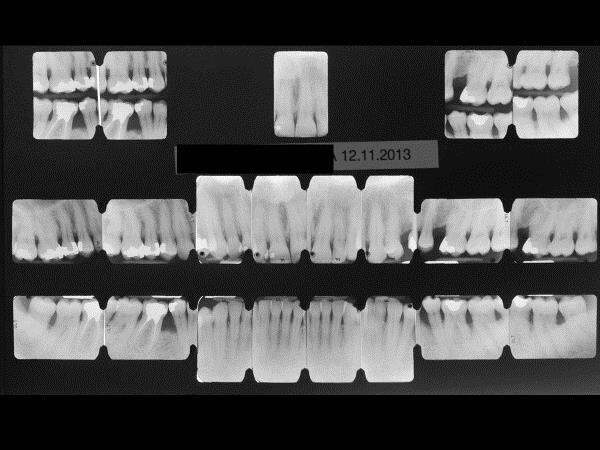

Una congrua igiene domiciliare può influenzare in modo significativo le condizioni di salute orale. È un concetto noto, ma più che mai in questo periodo merita di essere avvalorato. In occasione di ogni congresso/evento, a cui ho avuto l’onore di partecipare, la prima diapositiva, dopo quella introduttiva dell’argomento, con il titolo della presentazione, è quella riprodotta nella figura 1a. Tale diapositiva voleva sottolineare quali erano le premesse e le conclusioni dei concetti illustrati nella conferenza. I fattori più rilevanti, nel determinare il successo di un trattamento odontoiatrico, in particolare di una gestione non chirurgica, in presenza di una infiammazione placca-indotta, sono quelli evidenziati dal cerchio azzurro (Fig. 1a). Certamente l’impegno del clinico in una ri-motivazione continua di ogni soggetto in cura è il principale in ordine di importanza, a seguire una efficace terapia eziologica, che mira a rimuovere professionalmente la noxa patogena, composta da biofilm. La cavità orale umana ospita un complesso microbioma composto da batteri, protisti, archei, funghi e virus1, 2. È dunque ricco di batteri e presenta una componente virale, di cui, proprio al giorno d’oggi, possiamo capirne il potenziale aggressivo. Terzo punto chiave: l’approccio non chirurgico dovrebbe essere sempre la prima fase di trattamento, seguita eventualmente da una gestione chirurgica del caso, se non si sono raggiunti gli obiettivi o una stabilità clinica, che soddisfa le aspettative del paziente e del team odontoiatrico. Tutto ciò che viene elencato nella diapositiva, al di sotto del cerchio azzurro (Fig. 1a), riguarda una serie di apparecchiature, prodotti, sostanze, medicinali, eccetera, che pur trovando indicazioni, sono sempre aggiuntive e mai da utilizzare come monoterapia3.

Frequentemente nelle fasi iniziali di un impegno didattico, presentavo un caso che in primis aveva sorpreso anche me, per la sua evoluzione positiva, ma che mi permetteva di oggettivare quanto rilevante fosse la performance domiciliare del paziente e la sua adesione alle raccomandazioni di igiene orale, fornite in modo sempre personalizzato alle esigenze individuali di ciascuno.